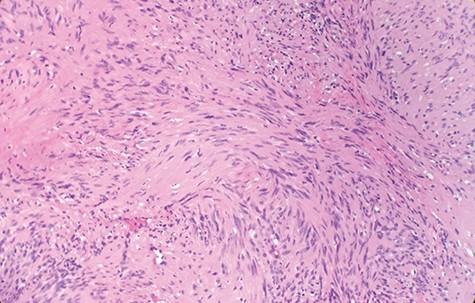

Macroscopically, the tumor appeared encapsulated, rubbery and pink-tan in color. Microscopic examination reveals that tumor composed of biphasic spindle hypercellular Antoni A areas and hypocellular Antoni B areas (Fig. 1). Higher magnification reveals that spindle tumor cells are narrow, elongate, wavy with tapered ends interspersed with collagen fibers (Fig. 2). Immunohistochemical staining revealed that most tumor cells reacted strongly for S-100 protein (Fig. 3). Combined with immunohistochemical profile, these histological features are diagnostic of benign schwannoma. Patient was discharged home on the same day as the operation. At the 1-month follow-up, he was symptom free, without any pain or sensory disturbances.

Microscopic examination reveals that tumor composed of biphasic spindle hypercellular Antoni A areas and hypocellular Antoni B areas (×2).

Diagnostic criteria for schwannoma requires a biphasic cellular pattern, consisting of two distinct regions namely Antoni A and Antoni B. Antoni A is hypercellular with eosinophilic cytoplasm, whereas Antoni B is hypocellular and has loose tissue comprising clear, vacuolated cytoplasm due to lipid accumulation. In addition, nuclear palisading is a typical feature and when pronounced forms Verocay bodies [4].